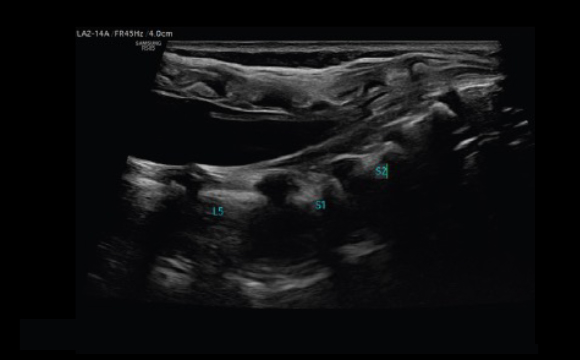

Mostra chiaramente la punta dell'ago

Con la massima precisione, NeedleMate+™ delinea chiaramente la posizione dell'ago durante l'esecuzione di interventi, come i blocchi nervosi. La precisione ed efficienza nella procedura è migliorata grazie anche alla presenza del beam steering aggiunto al NeedleMate+™.